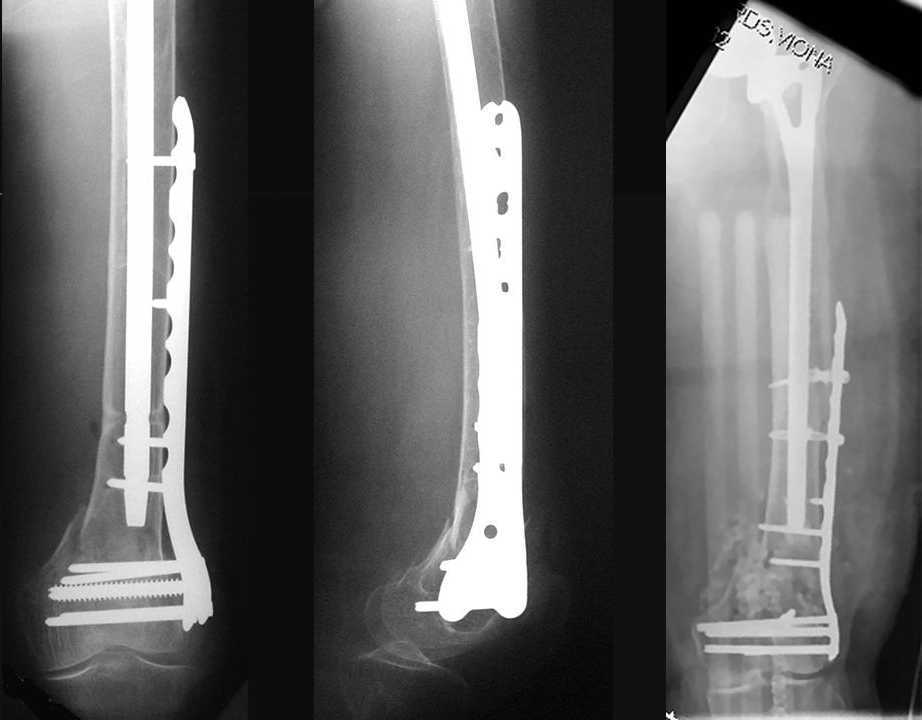

4. We could treat this fracture like there is no a nail - new locking plates allow for secure fixation.... two similar cases are attached...

Images sent by Professor Kanlic look nice, very good job. Excellent achorage in distal fragment. However, unicortical screwing or bicortical

makes a difference, also for locked screws. Proximal fragment unicortical fixation may present stability not easlily predictable. Certainly its stability for wheelchair should be sufficient. Full weight bearing can not be mentioned for this case. If minimal bearing is allowed full weight

Images sent by Professor Kanlic look nice, very good job. Excellent achorage in distal fragment. However, unicortical screwing or bicortical makes a difference, also for locked screws. Proximal fragment unicortical fixation may present stability not easlily predictable. Certainly its

stability for wheelchair should be sufficient. Full weight bearing can not be mentioned for this case. If minimal bearing is allowed full weight